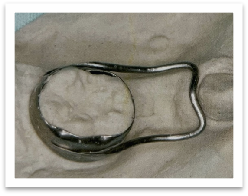

在后牙区比较常见的情况是乳牙早失后邻近的牙齿向前移位,占据了相应恒牙萌出的空间,导致牙齿萌出间隙不足而被卡在了骨头了出不来。为了避免这种情况,在乳牙早失后要及时做间隙保持器,维持住这宝贵的空间。

临床上制作的间隙保持器照片